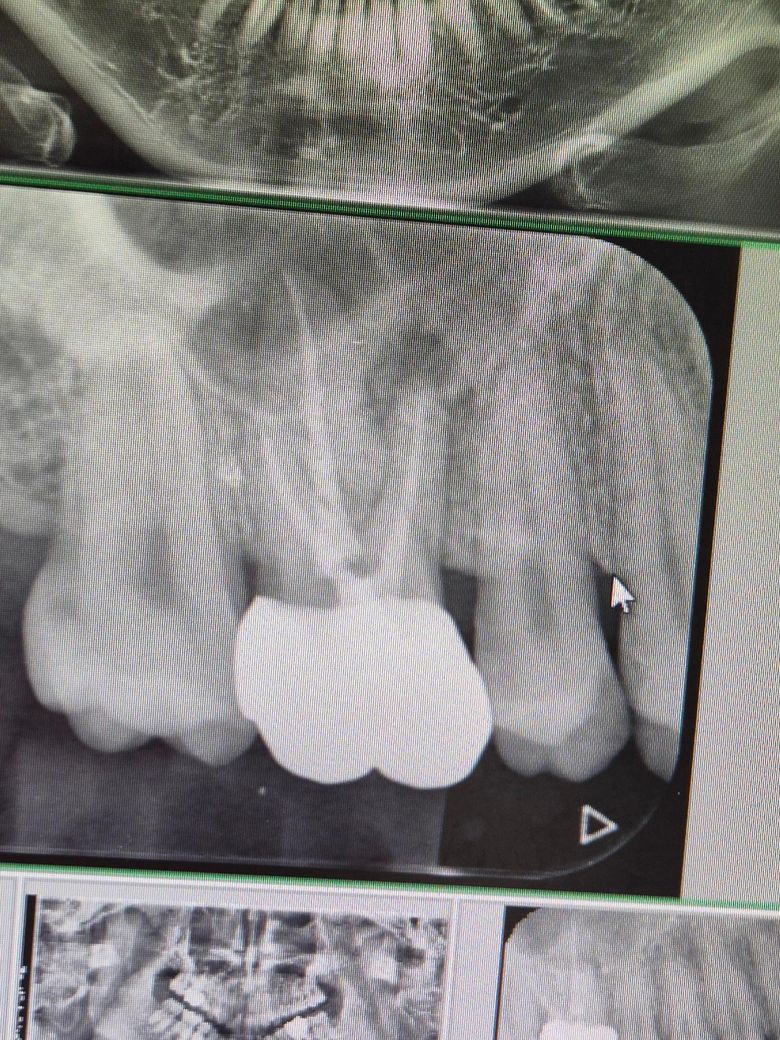

요 상태로 지금 2~3년 지났습니다 통증은 없고 잇몸 뿌리염증이 커지지 않으며 고름 주머니도 없는 상태입니다 재신경치료나 다른 치료를 하지 않아도 되나요?

• 1번 째 사진

이미 신경치료가 되어있고 보기에 퀄리티도 괜찮아보입니다 그래서 저 염증이 커지진 않는지 정기적으로 검사하면서 지켜보는 것도 방법입니다

아마도 신경관하나(mb2) 놓친게 있어서 거기서 비롯된 염증일거라 추정됩니다